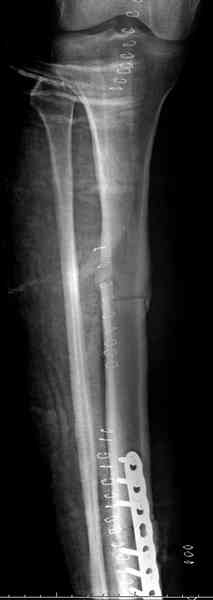

conference мы разбирали похожий случай, ложный сустав большеберцовой кости после резекции опухоли.

Оперирован в военном госпитале с заменой сегмента

аллокостью большеберцовой кости и после демобилизации явился для постоянного наблюдения по месту жительства.

Наши имели проблему со сращением, пришлось им сделать динамизацию, дополнительную аутопластику.

Снимки представлены.